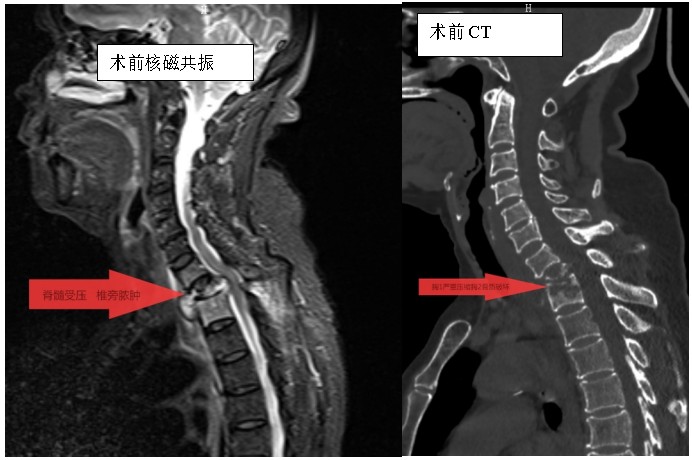

家住耒陽的70歲的李奶奶,因“頸胸背部疼痛不適伴雙上肢麻木6個月”,來到衡陽市中心醫(yī)院脊柱外科住院,住院當天,患者頸胸椎核磁共振顯示:胸1、2椎體骨質(zhì)破壞,伴胸1、2椎旁軟組織腫脹、同層面椎管變窄,因脊髓受壓而導致頸胸背部疼痛。在錢軍博士帶領(lǐng)下,醫(yī)療團隊詳細予以完善相關(guān)檢查后,研究患者的臨床資料,考慮脊柱結(jié)核并椎旁膿腫的可能性大,由于患者胸1椎體病理性骨折并椎管狹窄,遂囑患者嚴格臥床休息,術(shù)前給予標準四聯(lián)抗結(jié)核藥物治療2周,以控制活動性結(jié)核感染,降低術(shù)中播散風險,并嚴密監(jiān)測肝腎功能及血常規(guī)情況。